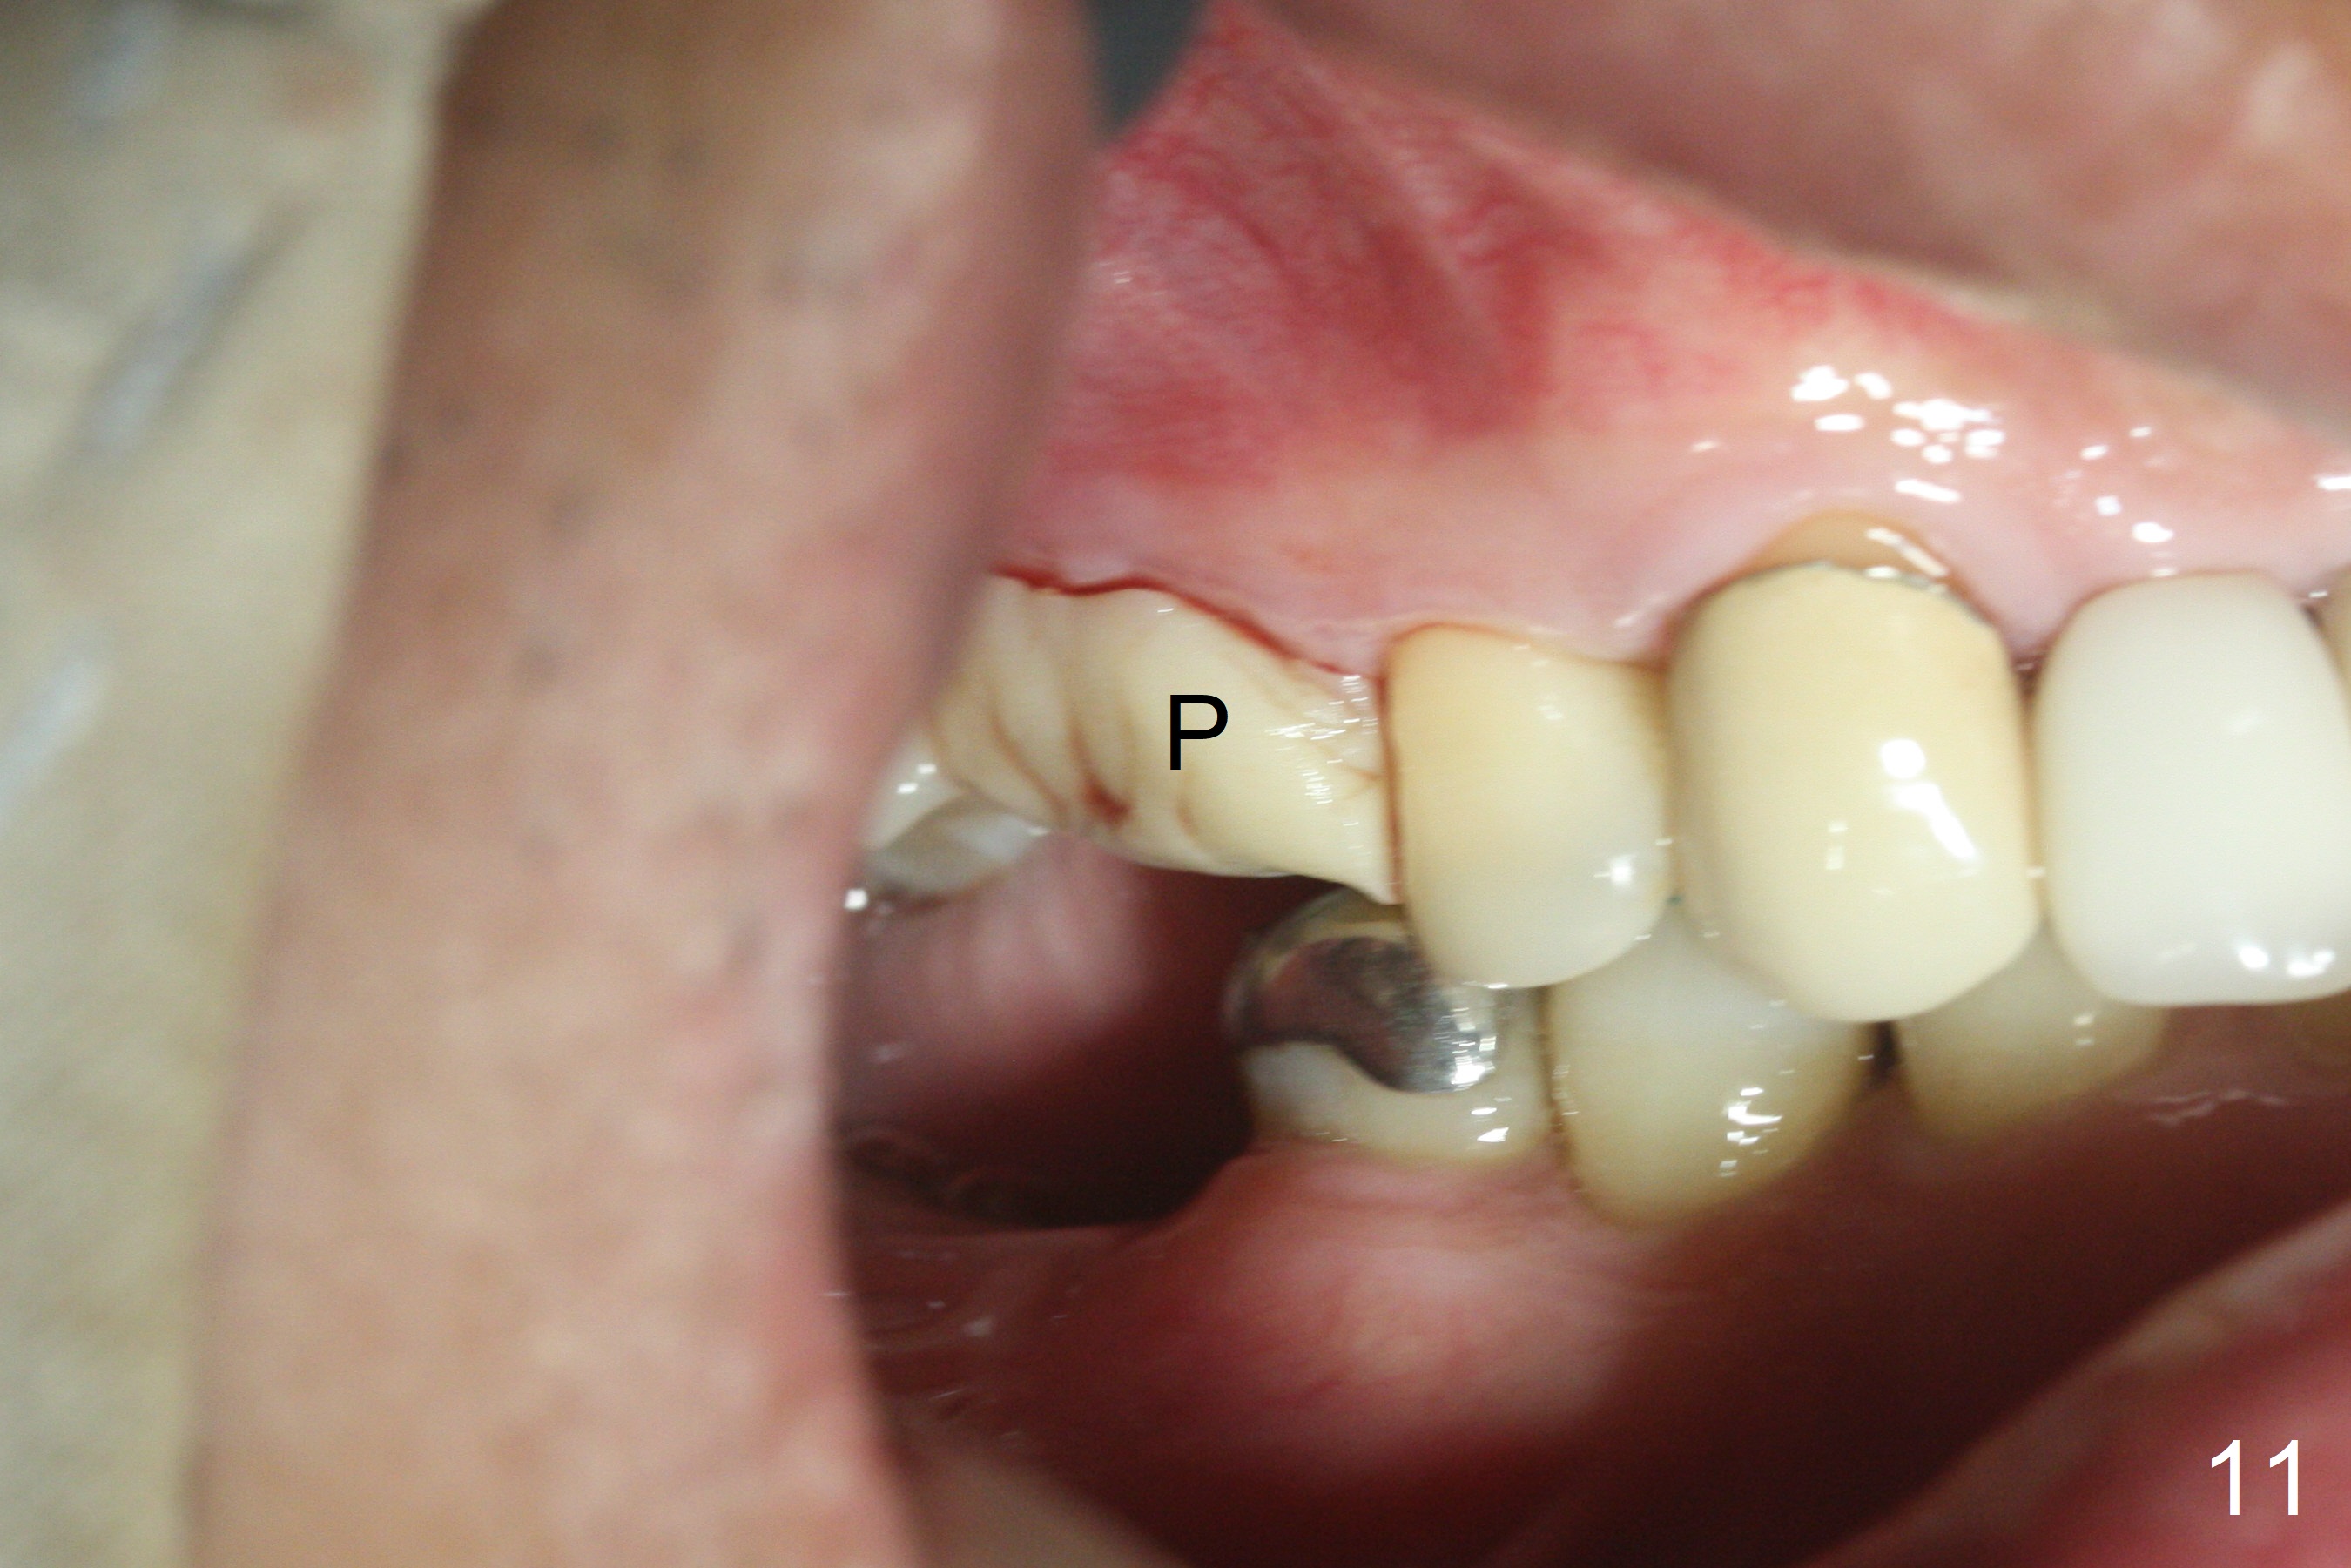

The palatal cusp of the affected 2nd premolar is apparently rotated distal (Fig.1). It is more obvious for the socket (Fig.2): the palatal (P) portion of the socket is more distal than the buccal (B) one. When the gauze is removed (Fig.3), Lindamann bur is used to remove the disto(D)palatal bone of the socket (data not shown), followed by starter drill in the DP wall obliquely (Fig.3'). Once the drill enters the bone for 1-2 mm, the bur is straightened and pushed slightly distal (Fig.3''). Fig.4 shows a parallel pin distal (overcorrect) to the original socket (Fig.4 red dashed line). Sequential osteotomy is conducted until 3.8x13 mm drill for 18 mm (Fig.5): note the 2 steps of the osteotomy (red lines). Since the apical portion of the osteotomy is larger than the drill, a larger implant than expected (5x16 mm) is placed. The implant ends up in the middle of the edentulous area (due to the stepped osteotomy; Fig.6-9; >60 Ncm). Vera allograft is placed (Fig.7-9 *) prior to and after placement of a 6.5x4(3) mm abutment (Fig.8-10). The remaining socket opening is sealed with a piece of Collagen plug (Fig.10 *). The socket is then closed by an immediate provisional (Fig.11 P). The abutment is retightened 2 months postop (Fig.12,13). The crown is cemented 4.5 months postop. Panoramic X-ray and CT are taken nearly 7 months post cementation (Fig.14,15) when the patient is ready for #30 implant guide preparation.